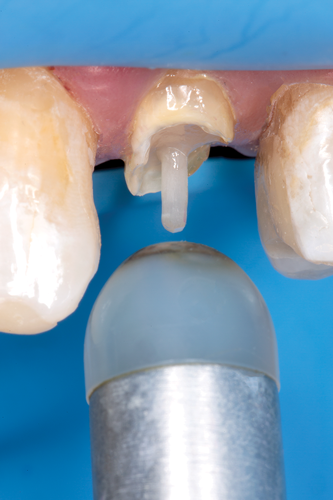

After completion of the endodontic treatment and crown lengthening to develop an ideal ferrule effect (Figure 3 through Figure 5) a diagnostic wax-up was fabricated to an ideal coronal preparation geometric shape, dimension, and height for the anticipated final composite core buildup (Figure 6). A clear polyvinyl siloxane (PVS) impression material was injected into a nonperforated tray, placed over the diagnostic wax-up, and then put into a pressure pot with cold water for 5 minutes. This procedure is aimed at reducing the potential for the formation of voids and bubbles in the impression material (Figure 7 and Figure 8). A small opening was made above the tooth to be restored using a tapered diamond bur (6847) (Figure 9). It is important to clean the internal surfaces with a microbrush to prevent silicone debris from integrating into the flowable material. Prior to the restorative procedure, a diagnostic wax-up was fabricated to the anticipated extracoronal contours for development of the final crown (Figure 10).

Fig 6. A diagnostic wax-up was fabricated to an ideal coronal preparation geometric shape, dimension, and height for the anticipated final composite core buildup.

Figure 6